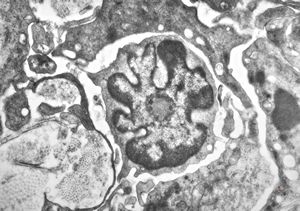

F, 48y. | lupus erythematodes … multiplicated vascular basement membrane

F, 48y. | lupus erythematodes … multiplicated vascular basement membrane

F, 48y. | lupus erythematodes … multiplicated vascular basement membrane